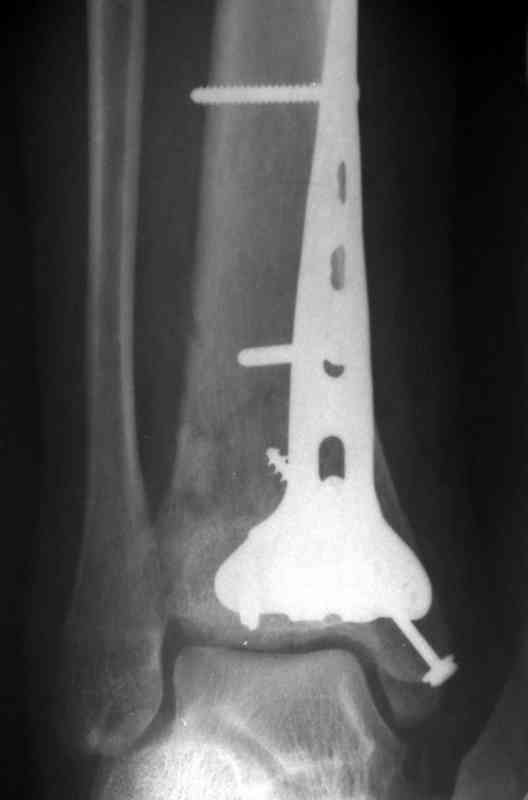

Отправитель: Дрягин В. 04 Январь 2007, 13:23

Посылаю результат лечения предыдущего больного через год.

Кстати, при переломах переднего края по классификации АО В-3 при переломах пилона пластина укладывается по передней поверхности. Она достаточно тонкая и эластичная, не надо этого бояться. Посылаю три снимка.